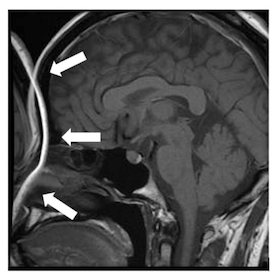

14-48 MR画像を以下に示す.描出されているものはどれか。3つ選べ。